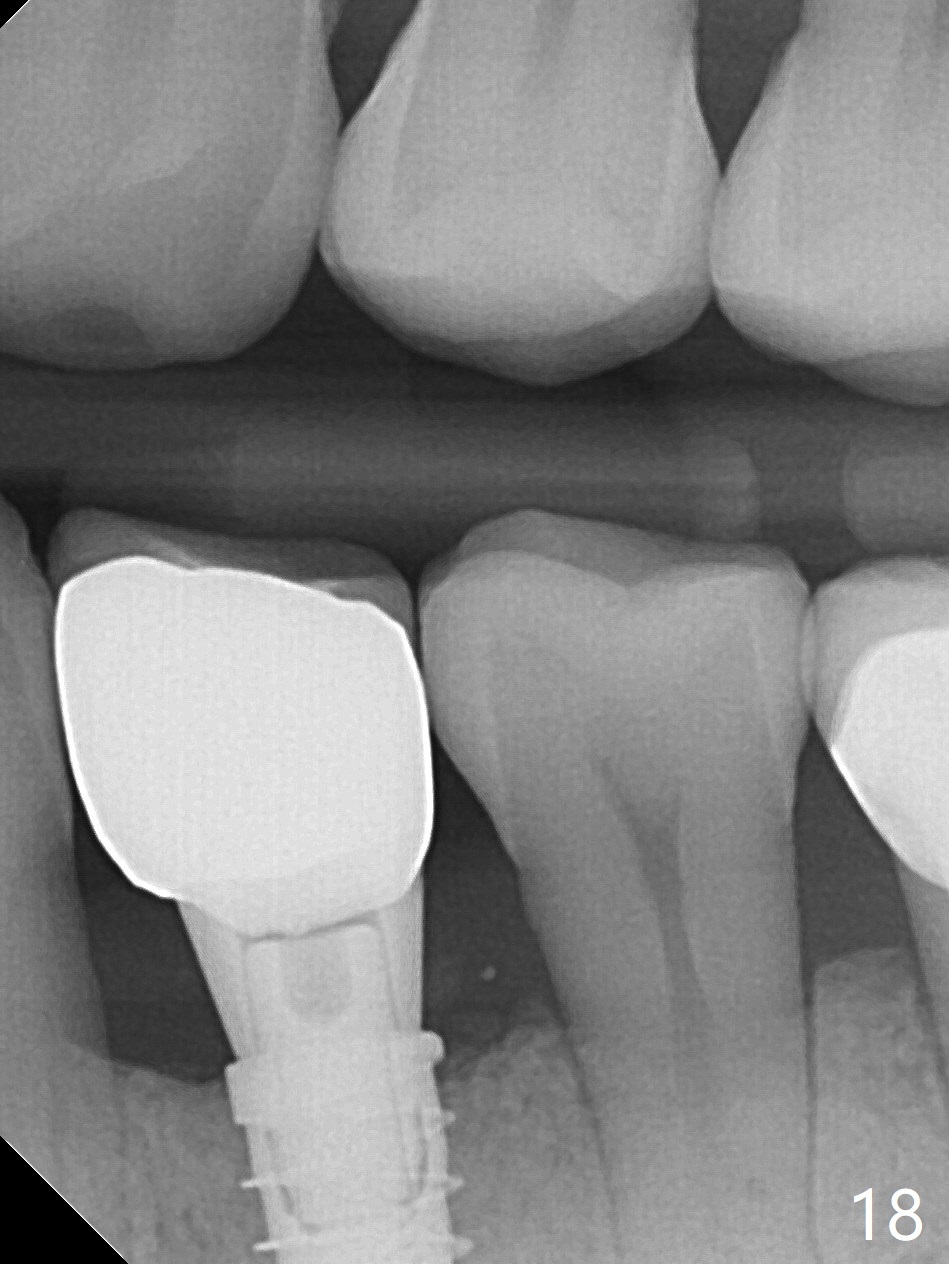

The patient returns for provisional revision 2 weeks postop (Fig.6). The bone graft remains in place (Fig.7). The buccal margin of the provisional is reduced (Fig.8).